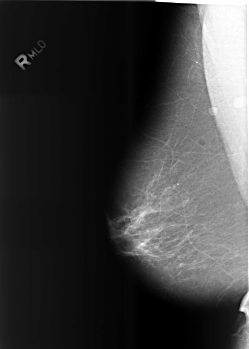

B_3466_1.RIGHT_MLO

RIGHT_CC LINES 5552 PIXELS_PER_LINE 3880 BITS_PER_PIXEL 12 RESOLUTION 50 NON_OVERLAY

RIGHT_MLO LINES 5576 PIXELS_PER_LINE 3984 BITS_PER_PIXEL 12 RESOLUTION 50 NON_OVERLAY